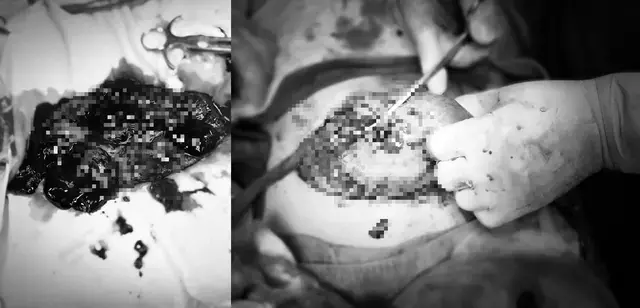

Sau khi thăm khám kỹ lưỡng, ê kíp y tế quyết định tiến hành phẫu thuật cấp cứu ngay lập tức. Khi mở ổ bụng, các bác sĩ phát hiện có nhiều máu cục và máu loãng tràn ra, cùng với một vết rách dài 4 cm ở vùng sừng phải tử cung đang chảy máu nghiêm trọng. Nhờ sự nhanh nhẹn và chuyên nghiệp, các bác sĩ đã kịp thời mổ lấy thai và khâu phục hồi tử cung. Trong suốt quá trình phẫu thuật, sản phụ đã mất khoảng 1.000 ml máu và cần truyền 2 đơn vị hồng cầu lắng cùng nhóm máu.